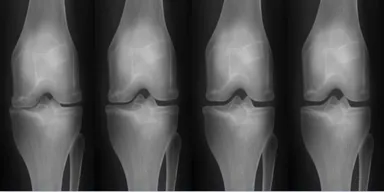

関節リウマチ(図1)や肝硬変(図2)など、特定の年齢層に限定されず、免疫力の低下で発生する可能性がある重症疾患の治療薬もやはりEHL BIOの核心研究分野です。両方の疾患ともに、既存の治療方式は「進行速度を遅らせること」に焦点を当てていましたが、EHL BIOが研究中の幹細胞治療剤の場合、患者本人の幹細胞の利用で免疫系拒絶反応を減らし「根本的な治療」が期待されます。

(図2)肝硬変(59歳, 男性)-施術後

脂肪幹細胞は何度培養しても遺伝子の変異がなく分化能力に優れているため、様々な自己免疫疾患の治療に利用されており、関節リウマチの炎症反応を抑制するのに効果的です。また、肝硬化幹細胞治療プログラムは、他人の幹細胞ではなく自分の脂肪幹細胞を使用するため、細胞拒絶反応や副作用がなく、安全に肝細胞を回復できる治療方法であり、一度の脂肪採取で十分な量の幹細胞を抽出して何度も治療できるという利点があります。